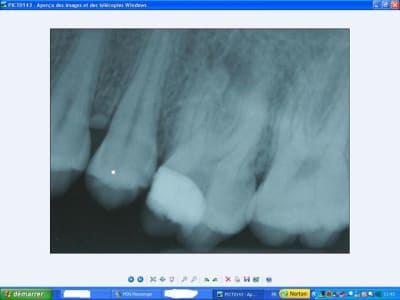

c'est pas un canal en C ? (incidence excentrée...:((.. dommage!). Je ne perds pas espoir

ben justement j'ai pensé à toi pour cette dent. J'avoue avoir été surpris de ne trouver qu'un seul gros canal, je pensais même avoir perforé le plancher lors de la trépanation... ouf!

j'ai donc cherché un canal en C mais après avoir bien sondé dans tous les sens + les loupes comme aide visuelle. Point de canal en C à l'horizon, désolé...